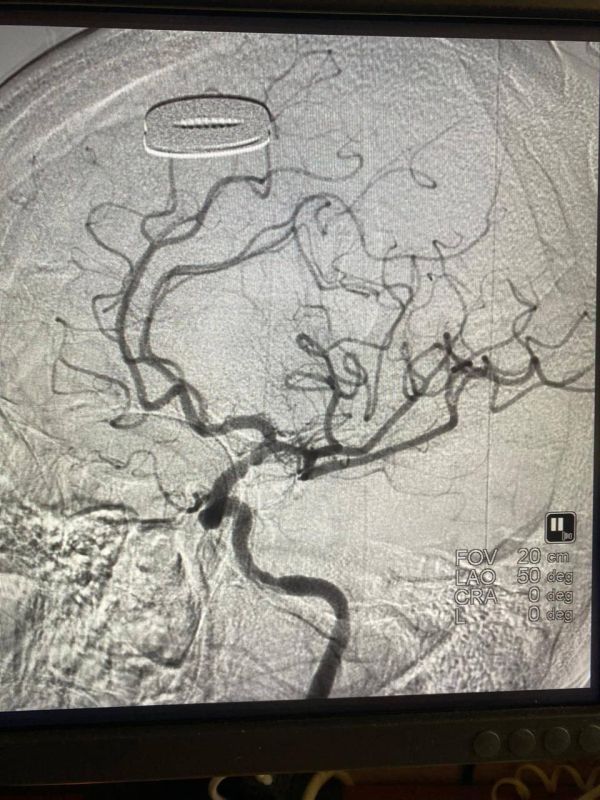

Она поступила в региональный сосудистый центр с комплексом симптомов тяжёлого инсульта.Неврологические функции тоже показывали отрицательную динамику: парез половины тела, отсутствие речи и угнетение...